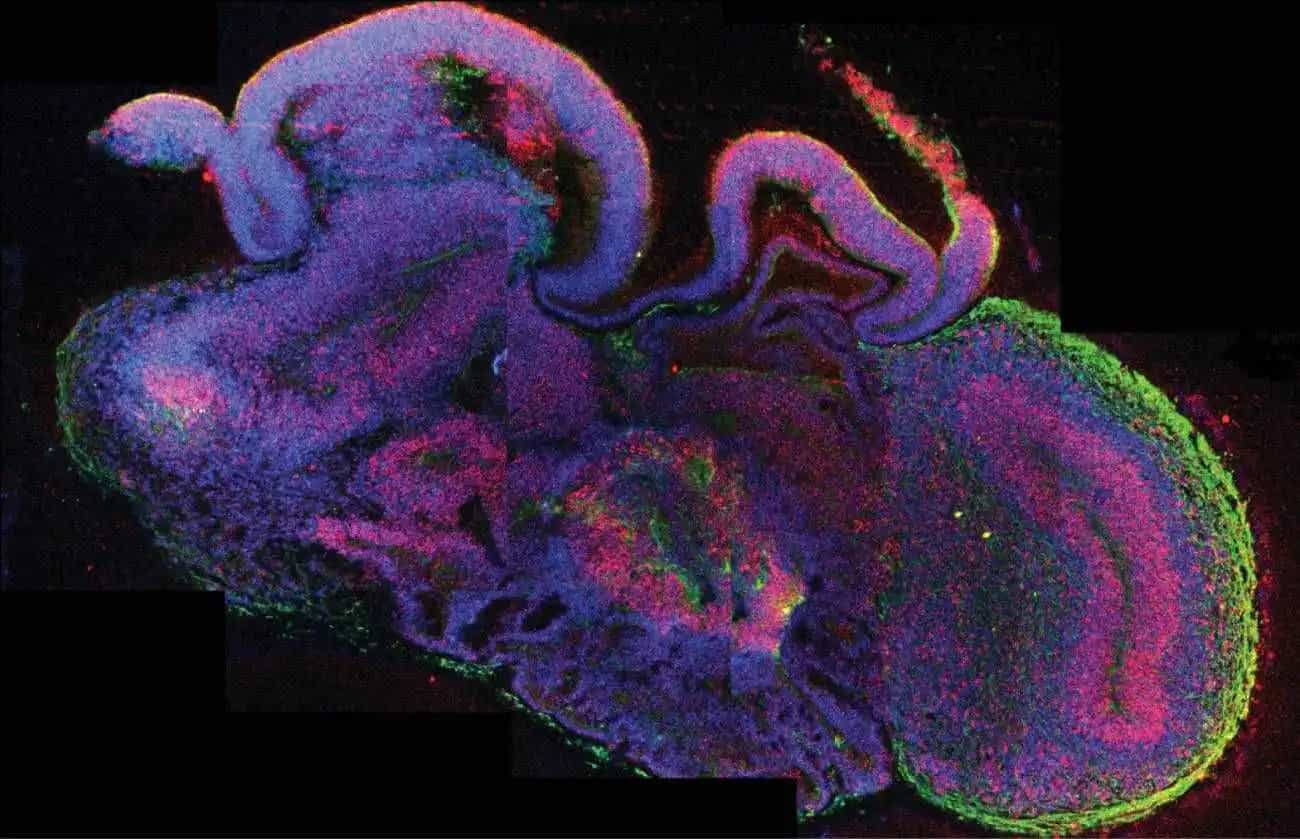

Investigadores de la Universidad Johns Hopkins han creado en laboratorio pequeños cerebros humanos que imitan varias regiones clave del cerebro real. Estos “mini cerebros”, llamados MRBO, no solo reproducen partes como el cerebro anterior o el tallo cerebral, sino que además presentan actividad eléctrica organizada y una red vascular incipiente, lo que los hace más parecidos que nunca a un cerebro humano en desarrollo.

¿Para qué sirven? Este avance permitirá estudiar enfermedades como el autismo, el Alzheimer o la esquizofrenia de una manera mucho más precisa. A diferencia de modelos anteriores, los MRBO integran múltiples zonas del cerebro al mismo tiempo, algo clave para entender cómo se conectan (o desconectan) ciertas funciones en trastornos neurológicos.

A diferencia de modelos anteriores, estos organoides integran múltiples zonas cerebrales y un sistema vascular básico, lo que los hace más parecidos a un cerebro humano real. Incluso comienzan a formar una barrera hematoencefálica, clave para probar medicamentos.

Además, podrían usarse en medicina personalizada, creando mini cerebros a partir de células de pacientes para estudiar sus casos específicos. Aunque aún tienen limitaciones, representan un paso clave para entender el cerebro y mejorar tratamientos neurológicos.